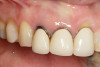

Fig 1. Clinical photograph showing significant issues related to implant midfacial mucosal recession and loss of interdental papillae. This is attributed to incorrect implant positioning (too buccal and too deep); several corrective surgeries resulted in interproximal bone loss, then loss of interdental papillae.

Figure 1